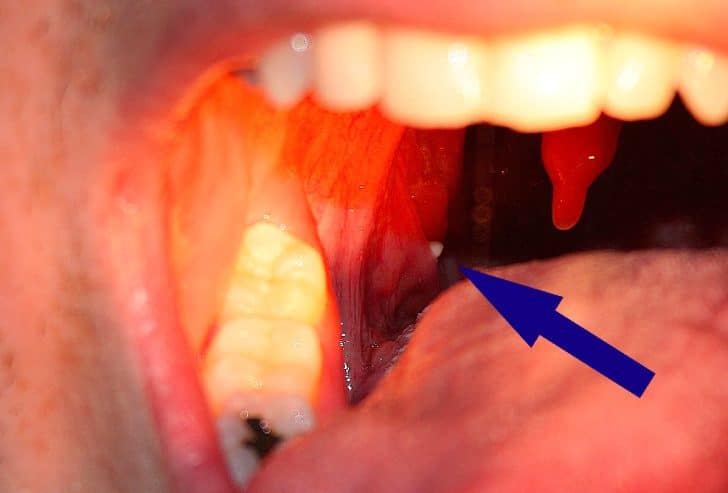

Tonsil stones, also called tonsilloliths, are hard, calcified formations that can develop in the crevices of your tonsils. Though they’re not usually harmful, these stones can cause discomfort, bad breath, and even throat infections. Understanding the causes and how to prevent them is essential for keeping your throat healthy.

Common symptoms of tonsil stones include persistent bad breath, a sore throat, difficulty swallowing, and ear pain. Some people might not experience any symptoms at all, which can make the condition harder to detect. If the stones become large, they can cause visible swelling in the throat and may even be mistaken for other conditions like throat infections or tonsillitis.